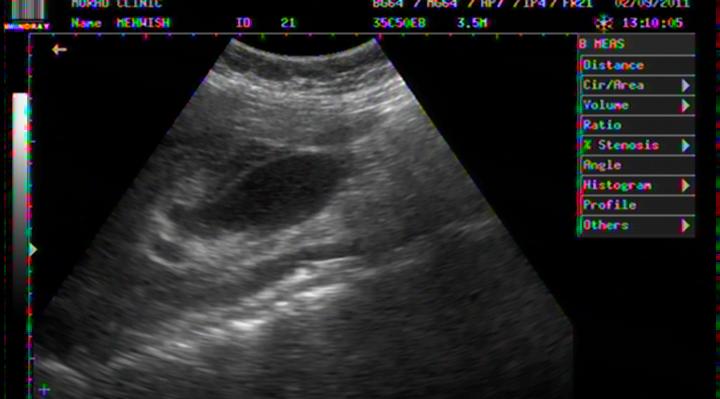

BILATERAL PLEURAL EFFUSION IN A 03 YEARS OLD BOY WITH DHF

BILATERAL PLEURAL EFFUSION COMPLETELY REABSORBED AFTER 3 WEEKS